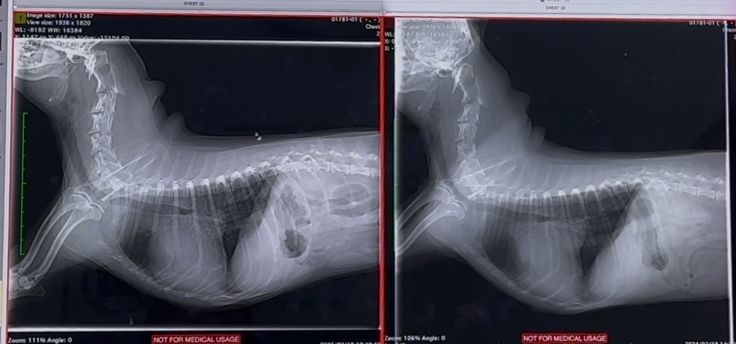

心臓手術後 1年半検診でした

心臓手術後、1年半検診でした

華の心臓は、術前、術後で

大きさはあまり変わっておらず

左心房の大きさは

今も、正常の倍はあり

逆流も、少し残っており…

右心の三尖弁逆流もあります

抗血栓薬を、今も飲み続けています

検査結果も、良くも悪くも…

現状維持でしたε-(´∀`;)ホッ